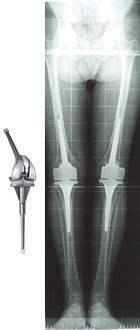

PROTESI VINCOLATE (CON FITTONI) - Si usano nelle revisioni, nelle gravi deviazioni assiali o nelle marcate instabilità del ginocchio. Permettono un ancoraggio e una stabilità dell’impianto maggiori. Sono impianti molto invasivi e per questo motivo il loro utilizzo è riservato a casi particolari.